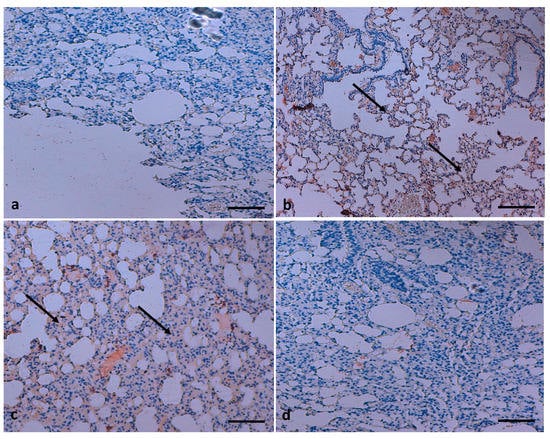

3. TQ Reduces NF-κB Expression in Lung Tissue

The excessive activation of macrophage plays a chief role in the development of lung injury. As is evident from ELISA results, TQ was found to have a key role in inhibiting NF-κB. Immunohistochemistry (IHC) staining demonstrated that a significantly high cytoplasmic NF-κB expression is found in the B(a)P-induced group compared to control rat tissue (Figure 9). NF-κB expression was considerably decreased in the B(a)P plus TQ treatment group in comparison with the group treated with B(a)P only.

Figure 8. Effect of TQ on lung fibrosis. (a) Normal fibre architecture of lung in control animals; (b) B(a)P administration induces severe fiber deposition; the arrow indicates deposition of fibers (c) TQ shows suppression of B(a)P-induced fibrosis, the arrow indicates less deposition of fibers and (d) normal fibre architecture observed in the group treated with TQ only. (Scale bar = 100 μm).

Figure 9. NF-κB protein expressional analysis. (a) The control rats did not express this protein; (b) the group treated with B(a)P only displayed high expression of NF-κB, the arrow indicates cytoplasmic positivity of NF-κB (c) the expression of this marker protein was reduced in animals co-treated with both B(a)P and TQ together, the arrow indicates cytoplasmic positivity of NF-κB (d) the animals treated with only TQ did not show any expression. (Scale bar = 100 μm.)